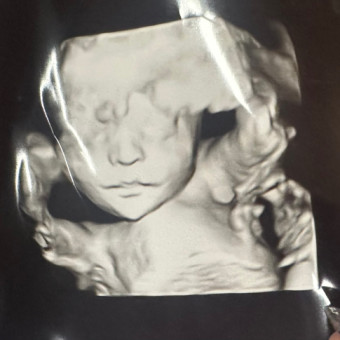

hello friends and family, a lot have asked for a registry so I have put one together, he is already so loved by his parents and we can not wait for him to be here! his nursery theme is woodland forest theme, if you wanting to get anything custom with his name on it please message me and I will tell you his name privately, some already know his name but we are trying to keep it a secret for the most part, thank you for all the love and support for our boy only a couple more months to go!